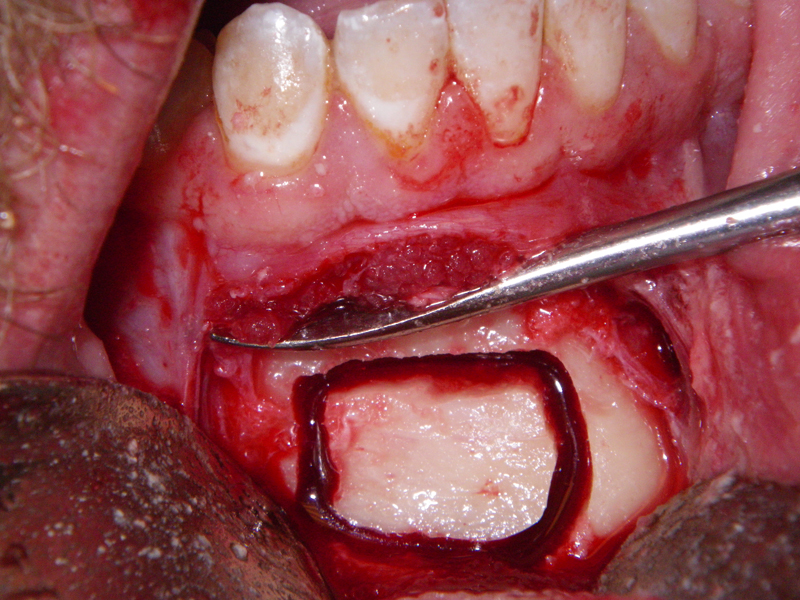

- Alveolar Ridge Augmentation

- Bone grafting – autogeneous, alogenic, xenogenic

- Blockgraft

- Incision

- Identify, don’t ‘skeletonize,’ mental nerves

- Midline, lateral score marks

- Osteotomy 5 mm below tooth apices & mental nerve

- Angulation of cut (Depends on planned movement)

- Downfracture (release ‘wings’)

- Fixation (plate, screws, wire)

- Layered closure (mentalis)